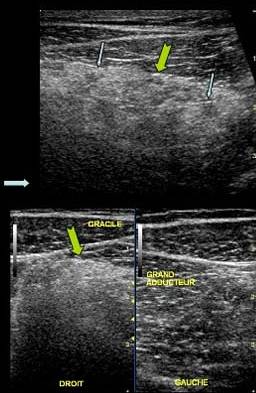

Ingrosare hiperecogema – stadiul 2 Rodineau

Stadiul III Rodineau – mica colectie lichidiana

Stadiul IV Rodineau – ruptura la jonctiune mio tendinoasa

Muschi retractat flotant in colectie hematica

Stadiul II Rodineau

Stadiul III Rodineau

Stadiul IV Rodineau